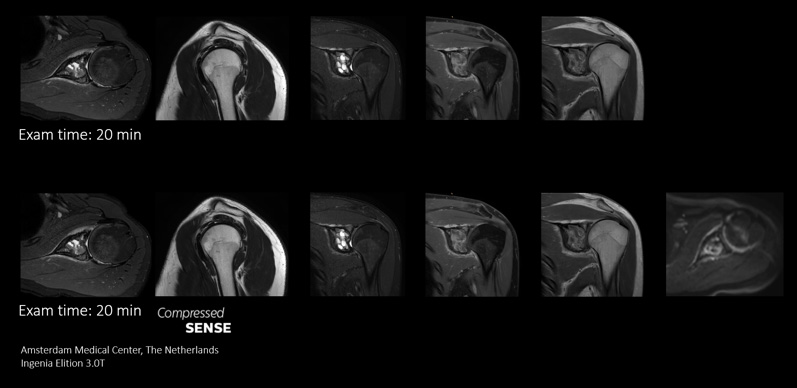

In conventional MRI scan techniques, high resolution imaging can involve long scan times which may be difficult for patients experiencing pain and discomfort. Long scan times can also make it difficult to fit high resolution imaging into acceptable MRI scan time slots for busy departments. Compressed SENSE enables fast 3D submillimeter (0.7 mm or less) isotropic images in less than 5 minutes to help diagnose challenging patients and anatomies.

This case demonstrates the ability to add additional sequences within the same time slot to enhance your diagnostic confidence. Besides traditional TSE sequences, you can now add a functional DWI sequence within the same timeslot, providing additional information for you to base your diagnosis on.